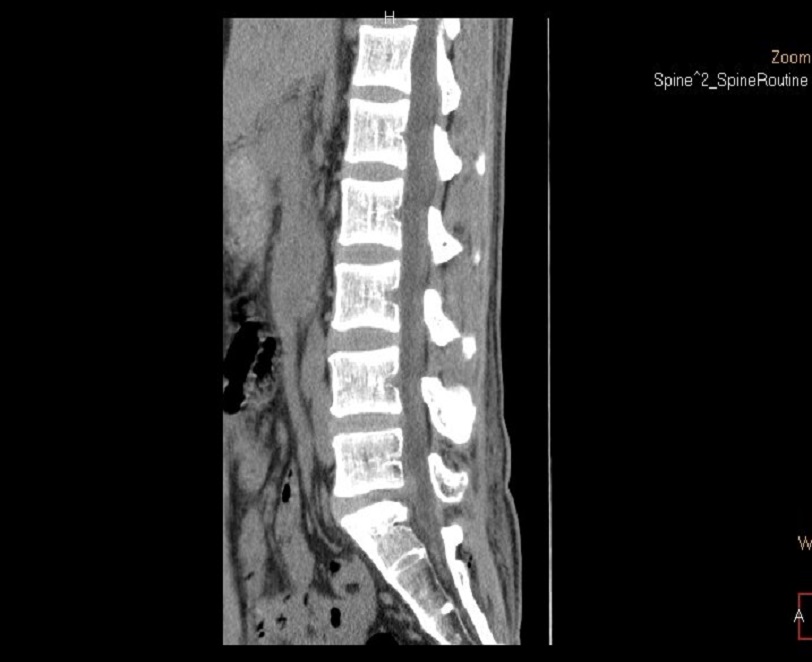

術后